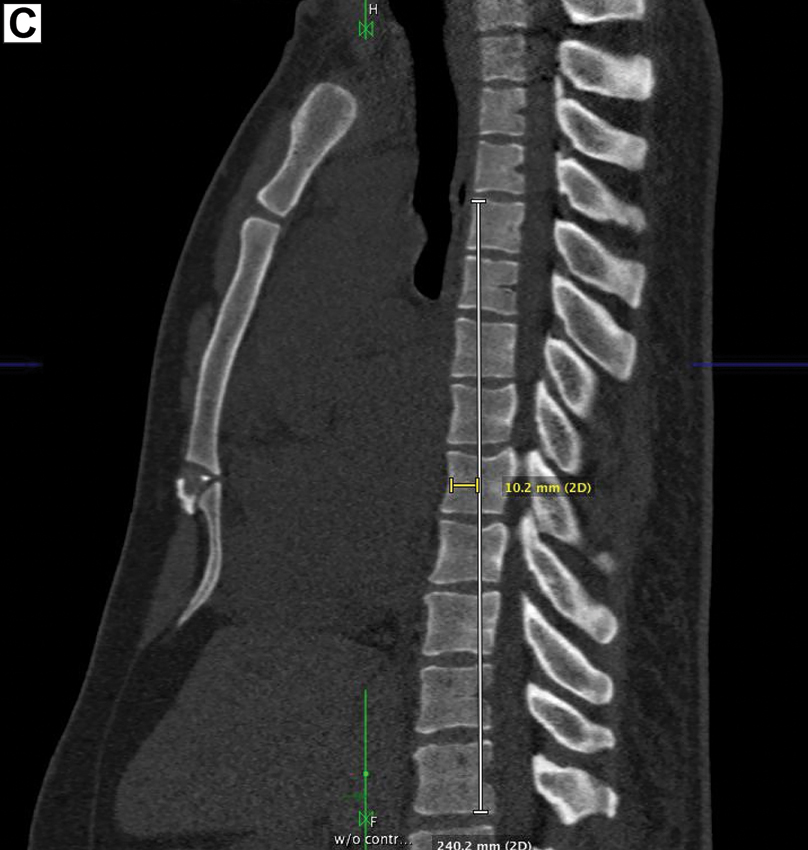

SBS is a congenital condition found incidentally during physical and radiographic evaluation. Diagnostic criteria include a ratio of the anteroposterior to the transverse diameter of less than or equal to 1:31 or a distance of 1.2 cm between the middle of the anterior border of T8 to a vertical line connecting T4 to T12 (image C).2 A pulmonic stenosis murmur was noted, presumed to be caused by compression of the right ventricular outflow tract by the SBS.3 Osteopathic manipulative treatment, such as high-velocity, low-amplitude techniques, may be used to improve somatic dysfunctions associated with this condition.3 No specific treatment is indicated.